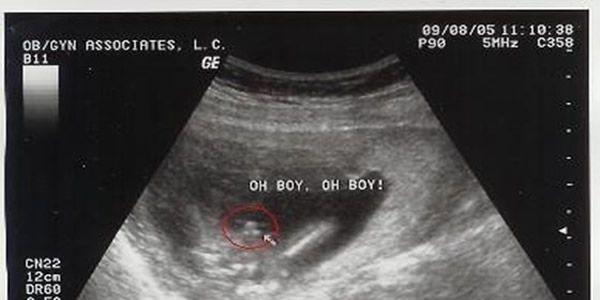

双腿间有三个亮点就是男孩,是直线就是女孩;

NT检查的时候是看不到这些类似于胎儿生殖特点的,因为NT检查在11-13周进行,这个孕周胎儿宝宝还太小,外生殖器也还未正式开始发育。通过NT检查看胎儿双腿间的亮点和白线进行性别判断并没有科学依据。

一般在4个月左右医生可以通过B超明确胎儿性别的。但是要看胎位情况,胎位好看时就准确,但不要太过相信判断。对于判断胎儿的性别来说,最直观的方法就是B超,B超下可以清晰的看清楚胎儿的各个器官和部位,包括生殖器。但是目前我们国家法律上规定,是不能擅自告诉孕妇胎儿的性别的,是属于违法的。